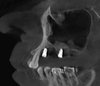

Стоматолог-хирург имплантолог

· Проведение хирургических вмешательств с фокусом на полную реабилитацию (All-on-4/6) с немедленной нагрузкой.

· Выполнение сложных костно-пластических операций, включая латеральный синус-лифтинг с одномоментной имплантацией.

· Активное внедрение цифрового протокола для планирования и проведения операций.

· Комплексная имплантация: All-on-4, All-on-6 (FP-1), одномоментная и отсроченная имплантация.

· Костная пластика: латеральный и крестальный синус-лифтинг, направленная костная регенерация (НКР), аугментация альвеолярного гребня.

· Работа с системами: Nobel Biocare, Straumann, Ankylos (Dentsply Sirona), Astra Tech, Osstem, Dentium, Bicon, AWI.

· Цифровые технологии: Работа с цифровыми хирургическими шаблонами, планирование в 3D-протоколах.